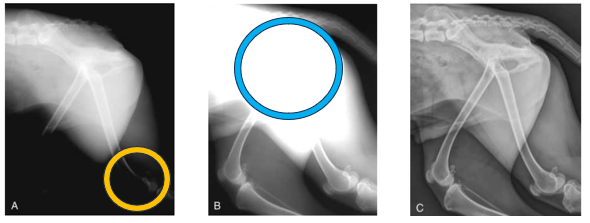

Advantage of CR and DR in regards to exposure - Yellow

The yellow circle indicates overexposure - this radiograph was created using film-based conventional radiography

The x-ray setting for the pelvis and lumber spine is ok but too high for the hindlimbs

Advantage of CR and DR in regards to exposure - Blue

Blue circle indicates underexposure

This radiograph was used using a film-based convention radiography

X-ray settings for the stifles/lower hindlimbs is ok, but not high enough for the pelvis and lumber spine

Advantage of CR and DR in regards to exposure

Perfect image quality